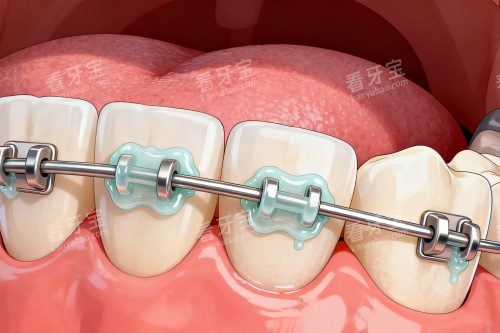

医院名称金属托槽自锁托槽隐形矫正人民口腔8000元起8000元起19800元起(时代天使)贝壳口腔4880元起--兆博口腔8000元起8000元起19800元起(时代天使)欢笑口腔4800元起7800元起8800元起(全隐形)省钱小贴士: 贝壳口腔和欢笑口腔的金属托槽矫正价格较低,兆博口腔和人民口腔的隐形矫正价格相近。如果预算有限,可以选择金属托槽;如果追求美观,隐形矫正是不错的选择。